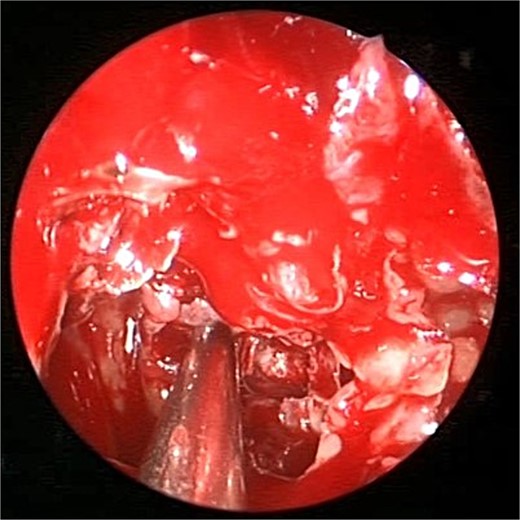

A 69-years-old diabetic female was referred from neurology as she complained of an acute onset severe headache, diplopia, and retro-orbital pressure. An initial CT scan with a subsequent MRI scan (Fig. 5) showed infiltrative sphenoid pathology invading both skull base and cavernous sinus given a provisional diagnosis of acute invasive fungal sinusitis. The patient was urgently taken to the operative theater to endoscopically debride sphenoid sinuses (Fig. 6). Histopathological examination confirmed the diagnosis of invasive sphenoid sinus mucormycosis.

Intra-operative endoscopic view of shenoid sinus debridement of invasive fungal disease.